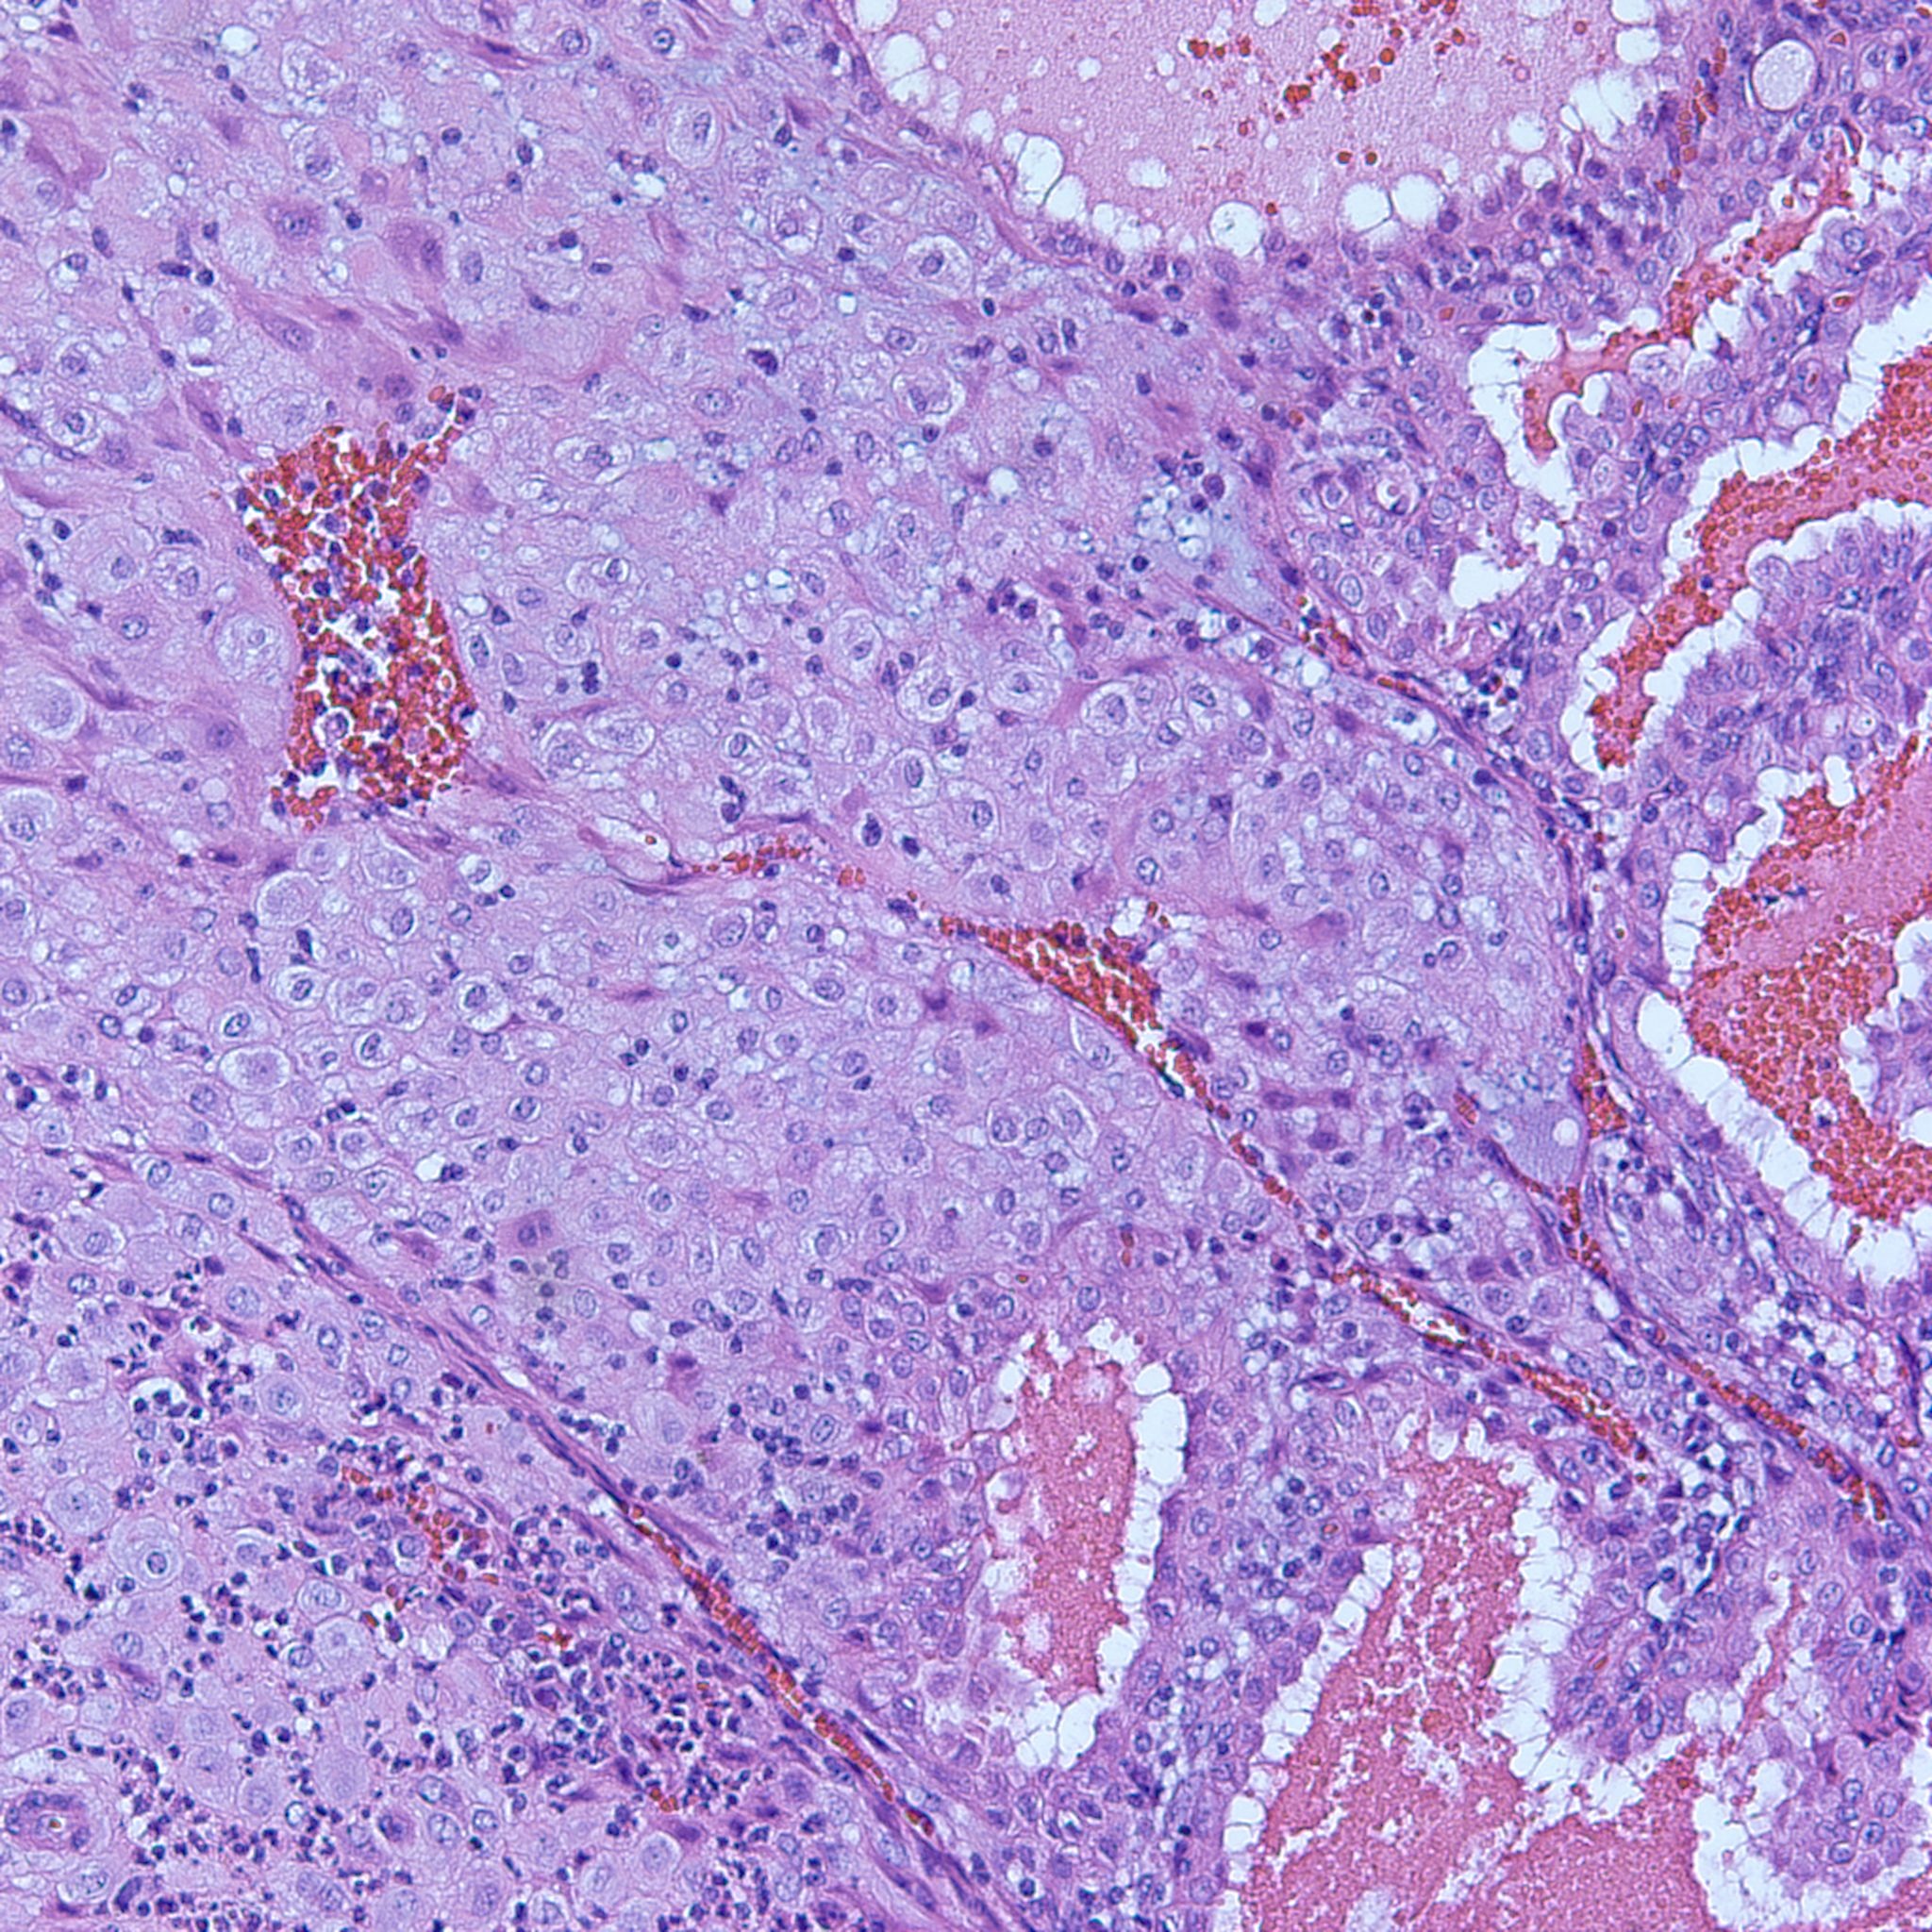

This large hydropic villus with central cistern also demonstrates an important finding: the loss of polarity of the surrounding trophoblasts with circumferential proliferation of variably atypical trophoblastic cells (arrows).